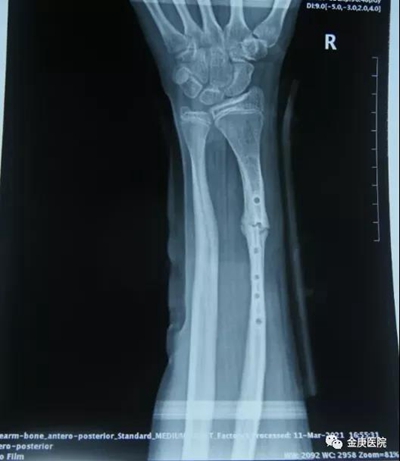

2021年3月,患者家長(zhǎng)慕名帶孩子來(lái)到金庚醫(yī)院找到了院長(zhǎng)宋兆普,他在外科專家徐發(fā)亮等配合下,只用了短短5分鐘時(shí)間,在不切口的情況下,完美將患者畸形尺骨斷開(kāi),而后又將橈骨與尺骨同時(shí)復(fù)位。從醫(yī)學(xué)檢查片看,對(duì)位可,手術(shù)成功,術(shù)后進(jìn)行外夾板固定,配合服用活血通絡(luò)和生骨接骨的院內(nèi)制劑,42天后,通過(guò)醫(yī)學(xué)檢查完全康復(fù)。

康復(fù)后

康復(fù)后的影像片